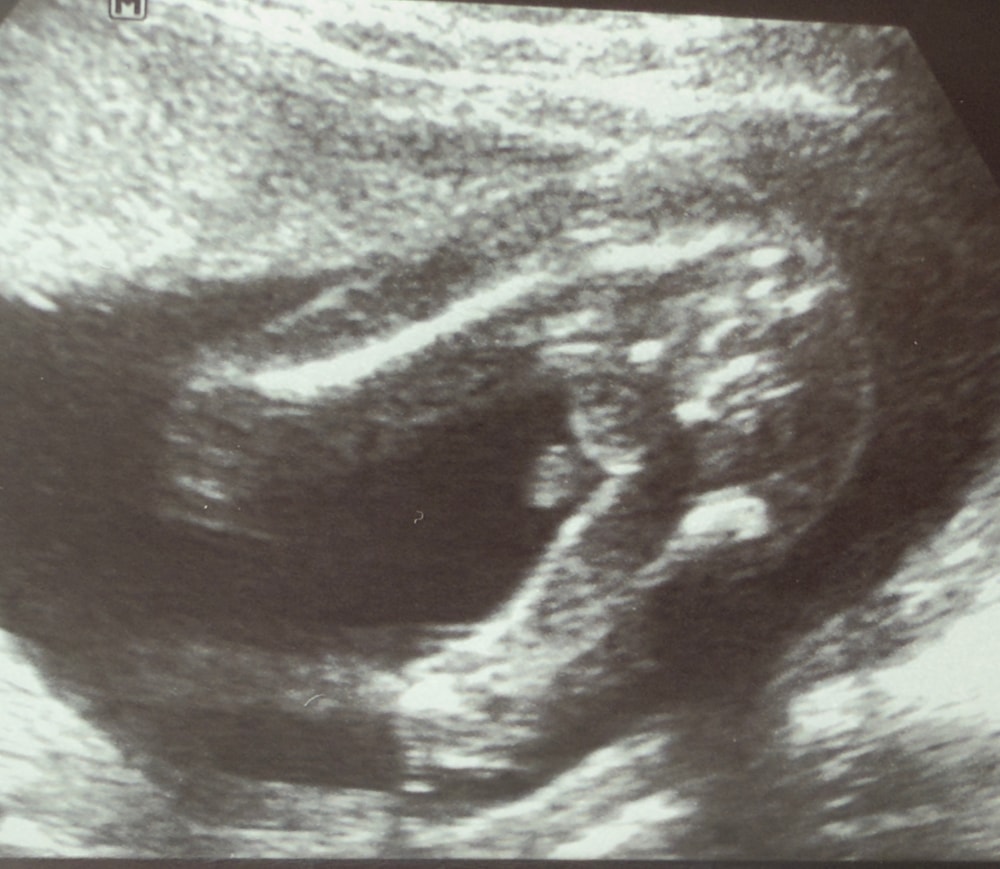

проведен второй скрининг в 19,3 недели.

Опытные глаза, посмотрите мой снимок УЗИ и скажите кто? Мальчик? (Фото будет в комментариях к вопросу). Как у Вас было с мальчишками?

Я пересмотрела разные снимки УЗИ в интернете и обнаружила, что мальчишеские прелести на снимке одним единым целым. На моем снимке будто по отдельности, мне кажется? И «пис» такой большой и странной формы.

Конечно мальчишка 👦

Всё отлично на снимке, парень))) ну и писы у всех разные, кому то большие, кому то крошечные😂